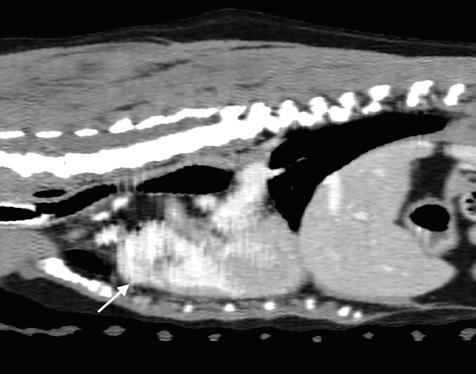

Se realizó una angio-TC de la cavidad torácica para caracterizar la masa mediastínica craneoventral. El estudio se realizó bajo anestesia general y con la paciente en decúbito esternal. Se realizaron series precontraste y post-contraste, inmediatamente y a los 3 minutos tras la administración de un contraste iodado hidrosoluble no iónico (iopromida 300 mg I/ml a una dosis de 600 mg I/kg intravenoso, administrado de forma manual) con cortes de 3 mm de grosor e intervalo 1,5 mm con algoritmo estándar (tejido blando) y pulmón. El estudio de TC se evaluó en ventana de tejido blando, hueso y pulmón, visualizándose en el área craneal al atrio derecho una estructura redon-

deada y bien definida (22UH) de medidas aproximadas 1,95 cm DV x 1,87 CrCd x 2,5 cm LL (Figs. 4 y 5). Tras la administración de contraste, esta estructura se llenó rápidamente de contraste de forma homogénea,

Figura 4. Imágenes de Tomografía Computarizada. Reconstruidas en plano sagital, simples (A) e inmediatamente tras la administración del contraste (B), en plano transversal, simples (C).

observándose una comunicación con el atrio derecho, midiendo el área de la comunicación 1,43 cm. El diagnóstico presuntivo fue de un aneurisma de la aurícula derecha.

Figura 5. Imágenes de Tomografía Computarizada. Inmediatamente tras la administración de contraste (A) en ventana de tejido blando. Se observa una estructura quística en la zona craneal del atrio derecho y que contacta con la aurícula derecha, rellenándose de contraste inmediatamente tras su administración (flechas blancas). (B) Imagen reconstruida en volumen rendering, donde se visualiza el aumento de tamaño de la aurícula derecha (flecha blanca).